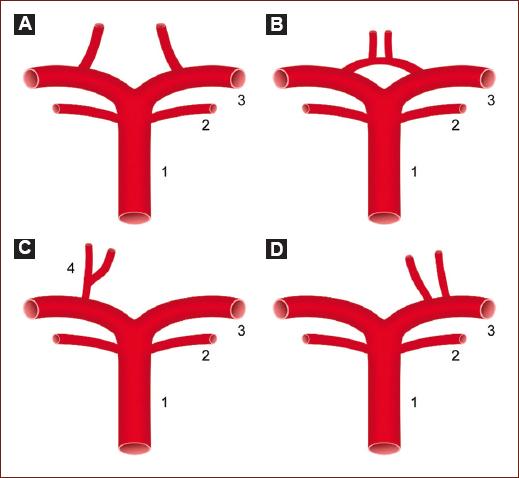

To the best of our knowledge, this retrospective case series is one of the largest reported in Colombia and Latin America (Table 2). While the prevalence of the Percheron artery remains unknown, it is estimated that this neurovascular variant could be present in up to 33% of the population (Fig. 2)9. Infarction of the Percheron artery accounts for 0.1-2% of all ischemic strokes10. Bilateral thalamic infarctions are rare, occurring in 22-35% of all thalamic infarctions11, with Percheron artery occlusion being responsible for 4-18% of this type of ischemic lesion10,12.

Figure 2 Anatomical variants of the thalamic paramedian arteries. 1. Basilar Artery. 2. Superior Cerebellar Artery. 3. Posterior Cerebral Artery (PCA). 4. Percheron Artery. A: paramedian arteries independent of the PCA (Usual). B: paramedian loop arteries. C: paramedian artery of Percheron (originates unilaterally in the P1 segment and then bifurcates, supplying the bilateral paramedian thalamus and rostral midbrain). D: both paramedian arteries originate from the P1 segment.